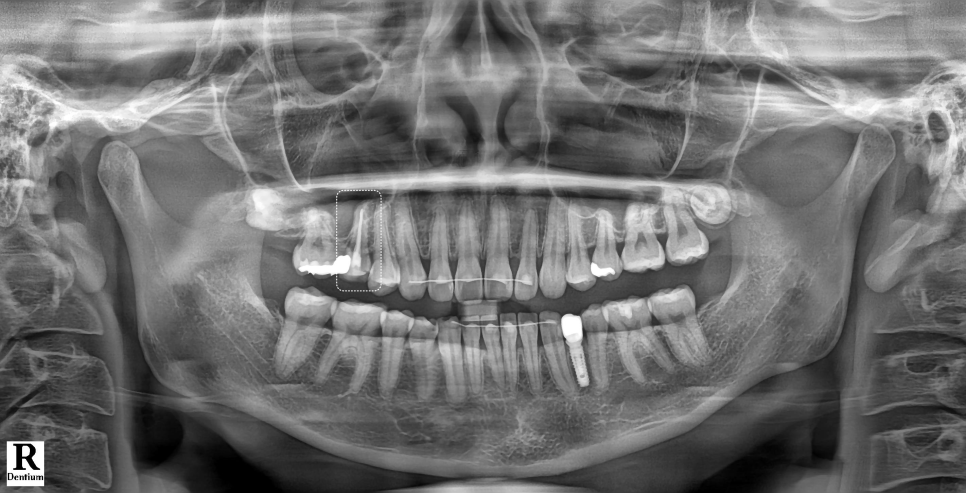

이미 타치과에서 신경치료가 마무리된 상태였고, 오른쪽 위 작은 어금니를 크라운 씌우기 직전이었습니다.

그리고 나서야 '신경치료 후 크라운 아닌 레진으로도 가능하다'라는 제 글을 보시고 속상하다며 연락을 주신 겁니다.

내원하셔서 확인해 보니 오른쪽 위 작은 어금니는 이미 신경치료가 끝난 상태였고 안은 임시 재료로 막혀 있었습니다.

촬영일 : 251124